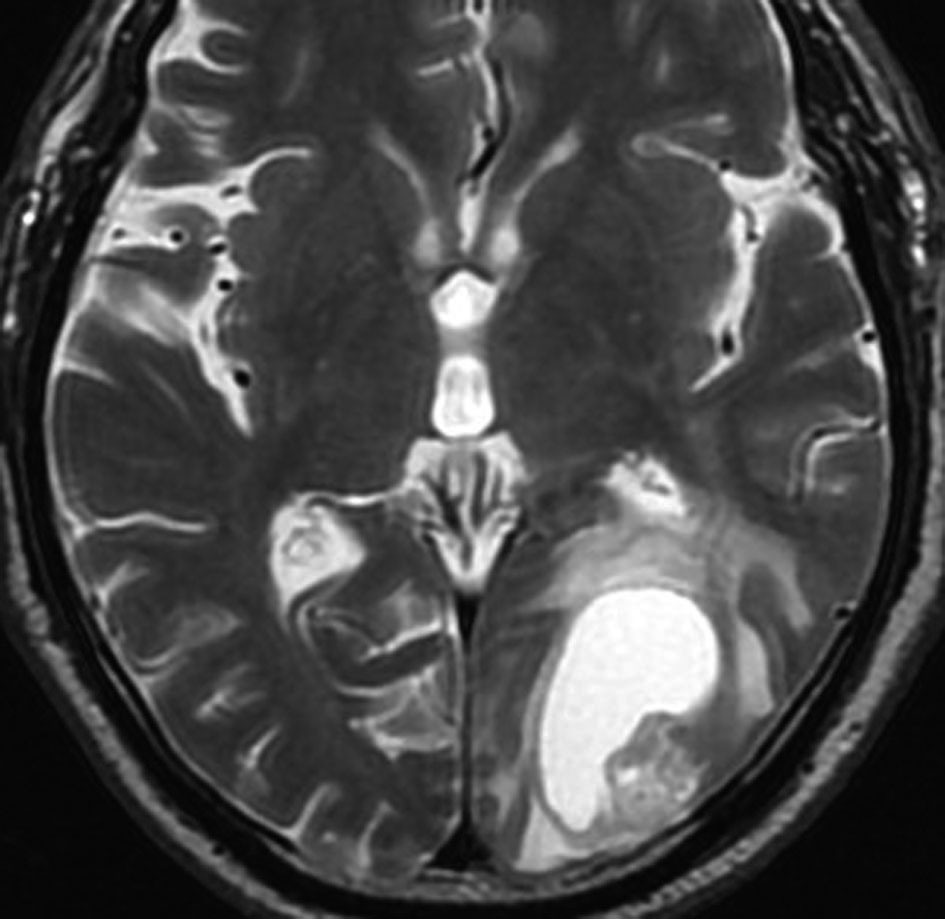

高齢者に発生したグリオーマです。左はガドリニウム増強MRIといいます。腫瘍の周囲が白く縁取られるように見えます。でも,右側のT2強調画像では,白く滲む部分が周囲に広がっています。

グレード3(かつての退形成性星細胞腫)かグレード4(膠芽腫),おそらく膠芽腫と「予想」できる画像です。確実ではないのですが,この予想は治療計画の上で重要なものです。